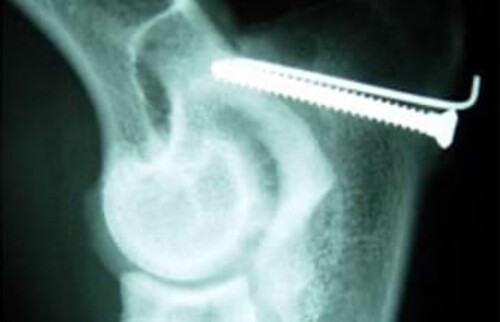

Wird der IPA vor dem 8. Lebensmonat diagnostiziert, gilt die Zugschraubenfixation mit begleitender Ulnaosteotomie als Methode der Wahl. Danach ist die Wahrscheinlichkeit eines Anwachsens durch die degenerativen Reaktionen an der Fuge so gering, dass man das Fragment entfernt, wenn es nicht bindegewebig fest verwachsen ist. Da der Prozessus Anconaeus über seine zapfenartige Form das Gelenk stabilisiert, wird die Entfernung immer zu einer degenerativen Gelenkveränderung führen und ist daher nie die Methode der ersten Wahl.

Berner Sennenhund, 6 Monate: Zugschraubenfixation mit Kortikalisschraube und Kirschner Bohrdraht.